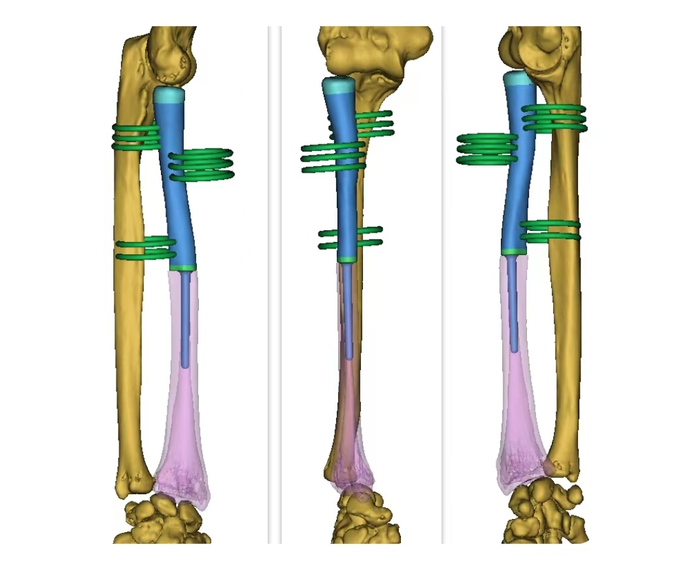

根据患者CT数据逆向生成骨骼模型

根据患者CT数据逆向生成骨骼模型依据临床医师要求,距病灶远端4mm截骨

假体根据截骨部分进行仿形设计,桡骨关节面为聚乙烯材料,并设置缝合孔,远端设计髓针嵌入剩余骨质,接触面为骨小梁结构,髓针长度50mm,根部直径5mm,末端直径4mm,髓针设计为水泥髓针